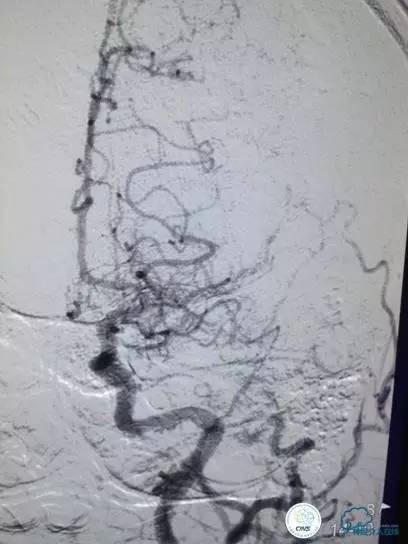

尿激酶20万单位,动脉导管内推注。

口服拜阿司匹林300mg,再次取栓。

2.0×15mm球囊扩张V4段狭窄。

Penumbra 导管再次取栓。

▼R-VA